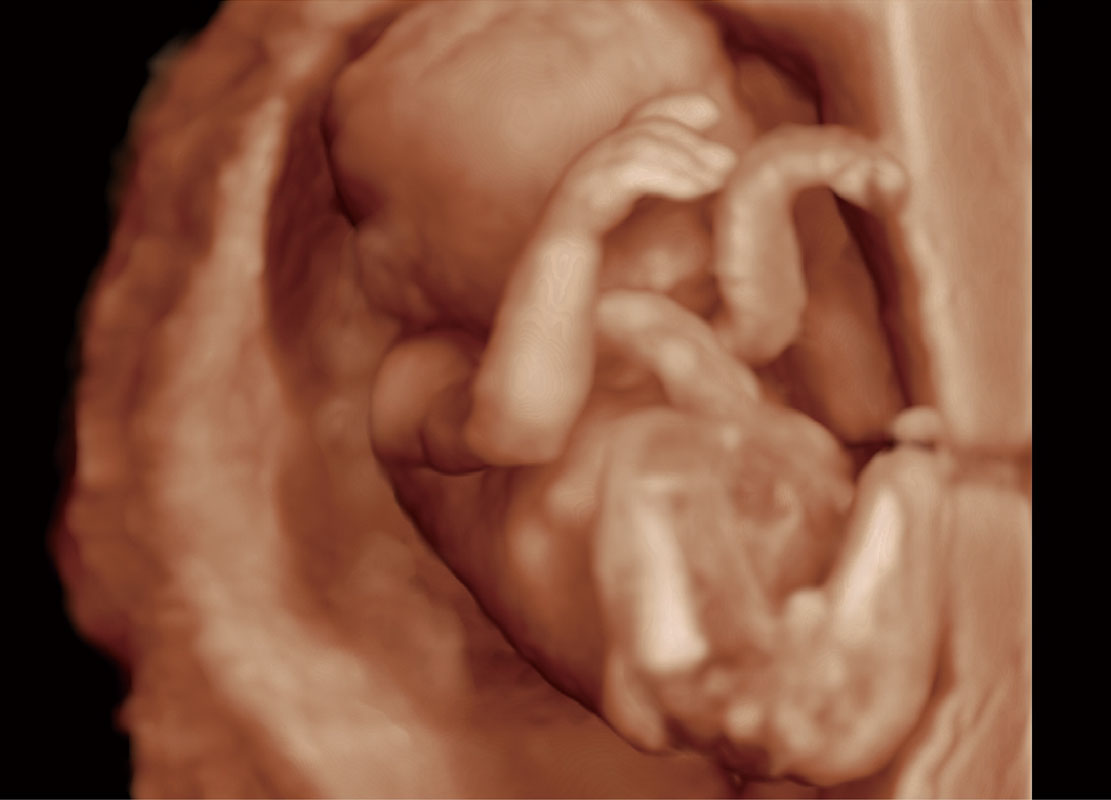

中晚孕筛查

P60提供简单易学易用的高端诊断工具,为您中晚孕筛查提供快速清晰的解剖信息。